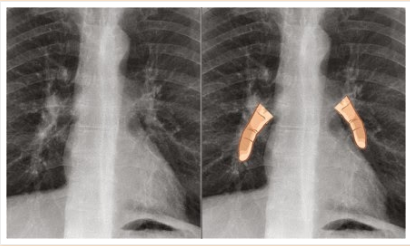

正常な肺門陰影の写真その1

Learning Radiology – Dense Hilum Sign